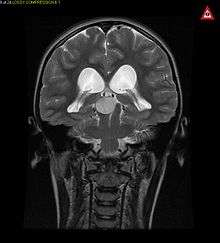

Pilocytic astrocytoma or juvenile pilocytic astrocytoma or cystic cerebellar astrocytoma (and its variant juvenile pilomyxoid astrocytoma) is a brain tumor that occurs more often in children and young adults (in the first 20 years of life). They usually arise in the cerebellum, near the brainstem, in the hypothalamic region, or the optic chiasm, but they may occur in any area where astrocytes are present, including the cerebral hemispheres and the spinal cord. These tumors are usually slow growing and benign.[1] The neoplasms are associated with the formation of a single (or multiple) cyst(s), and can become very large.

Pilocytic astrocytomas are often cystic, and, if solid, tend to be well-circumscribed. It is characteristically easily seen on CT scans and MRI.

Usually—depending on the interview of the patient and after a clinical exam which includes a neurological exam, and an ophthalmological exam—a CT scan and or MRI scan will be performed. A special dye may be injected into a vein before these scans to provide contrast and make tumors easier to identify. The neoplasm will be clearly visible.